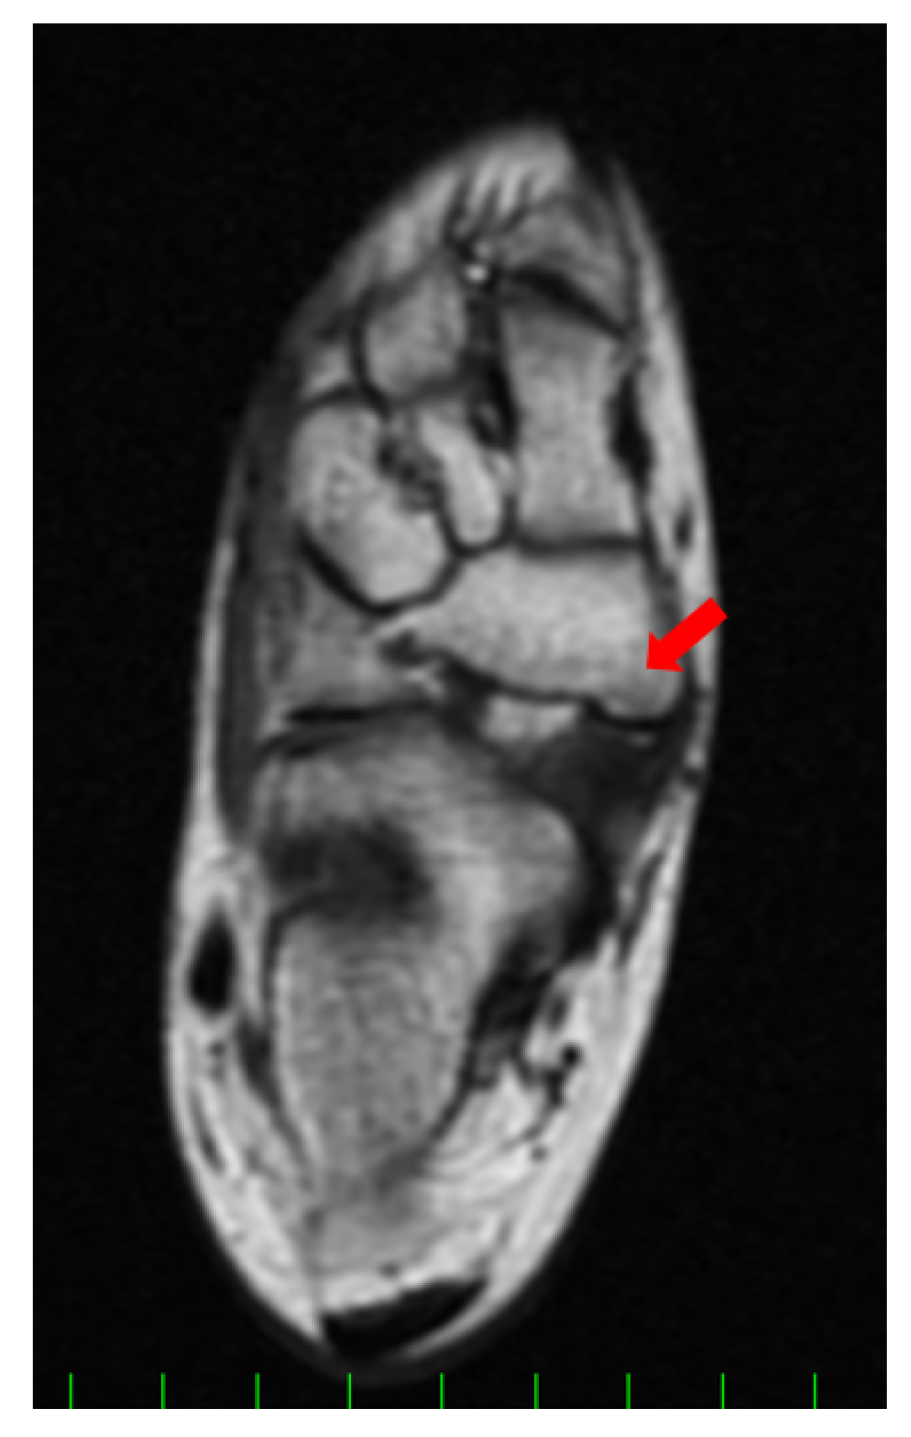

Figure 3.

Preoperative magnetic resonance imaging (MRI) finding (axial image, T1WI). A low signal lesion was detected in the prominent part of the navicular (red arrow).

Magnetic resonance imaging (MRI) showed that the lesion was iso-signal in both the T1- and T2-weighted images. The preoperative American Orthopaedic Foot and Ankle Society (AOFAS) hindfoot–ankle score [13] and visual analog scale (VAS) were 67/100 and 4/10, respectively. The preoperative foot and ankle outcome score (FAOS) [14] was as follows: symptoms, 71.4/100; pain, 61.1/100; function, daily living, 100/100; function, sports and recreational activities, 30/100; and quality of life, 18.8/100.